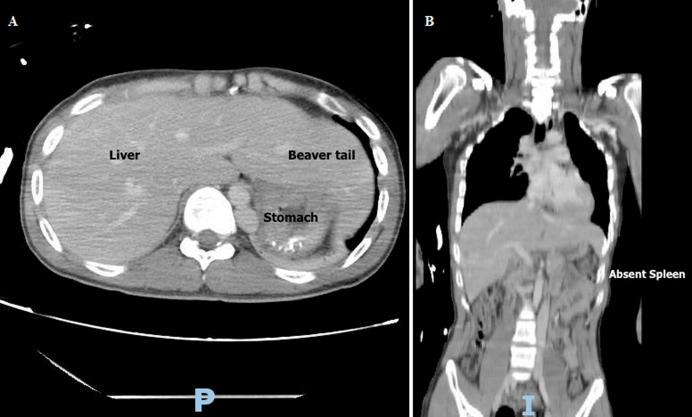

Beaver tail liver and congenital asplenia in a polytrauma patient.

https://cdn.ncbi.nlm.nih.gov/pmc/blobs/6786/10957729/5c42acb9d27b/PAMJ-47-18-g001.jpg